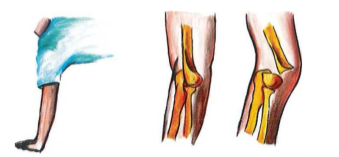

Ở trẻ em, cơ chế thường gặp là chấn thương gián tiếp. Có hai loại cơ chế chấn thương trong gãy trên lồi cầu xương cánh tay trẻ em

Gãy duỗi (chiếm 97% đến 99%): trẻ ngã chống tay, khuỷu duỗi hoàn toàn, đường gãy từ trước dưới đến sau trên, đầu gãy của đoạn trung tâm nhọn, di lệch ra trước nguy cơ tổn thương bó mạch và thần kinh cánh tay; đầu ngoại vi di lệch ra sau.

Cơ chế gãy duỗi trong gãy trên lồi cầu xương cánh tay trẻ em

Gãy gấp (ít gặp): trẻ ngã chống khuỷu, khuỷu gấp, đường gãy từ sau dưới đến trước trên, đầu gãy của đoạn trung tâm nhọn di lệch ra sau, có thể chọc thủng gân cơ tam đầu gây gãy hở.

Cơ chế gãy gấp trong gãy trên lồi cầu xương cánh tay